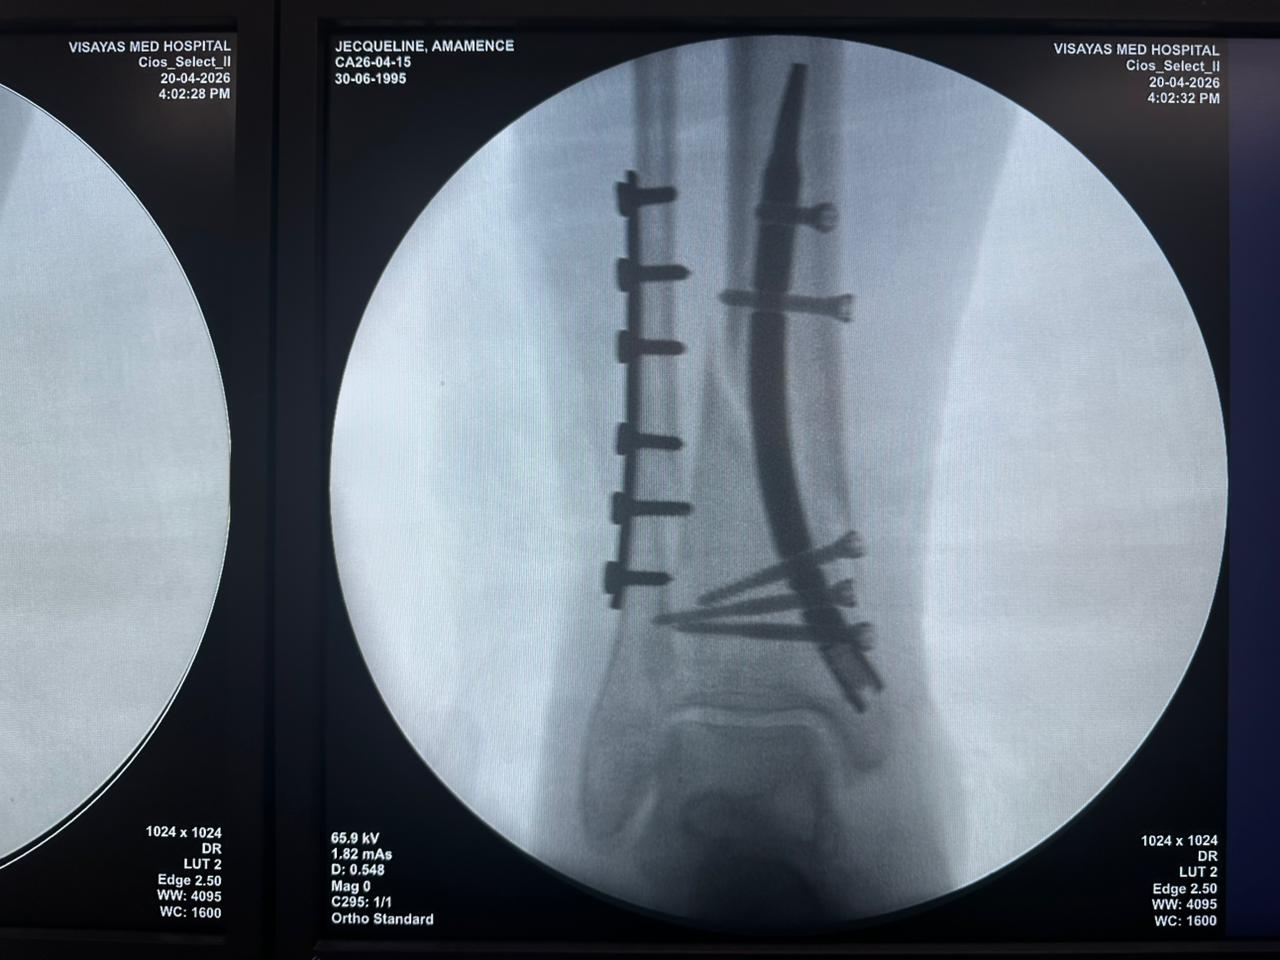

Radioscopie peropératoire de l'arceau, vues AP et latérales

Ce cas concernait une fixation tibiale distale à l’aide d’un clou tibial distal intramédullaire. La radioscopie peropératoire a confirmé la position du clou, des vis de verrouillage distales et de la fixation par plaque fibulaire.

Clou-tibial-distal-fluoroscopie-peropératoire-czmeditech (2)

Clou-tibial-distal-fluoroscopie-peropératoire-czmeditech (3)

Clou-tibial-distal-fluoroscopie-peropératoire-CZMEDITECH (4)

fluoroscopie-peropératoire-clou-tibial-distal-CZMEDITECH